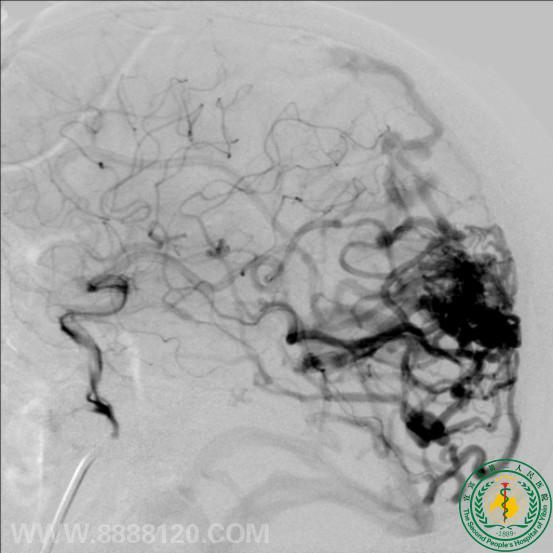

我科成功完成1例复杂动静脉畸形介入治疗

我科成功完成1例复杂动静脉畸形介入治疗9060